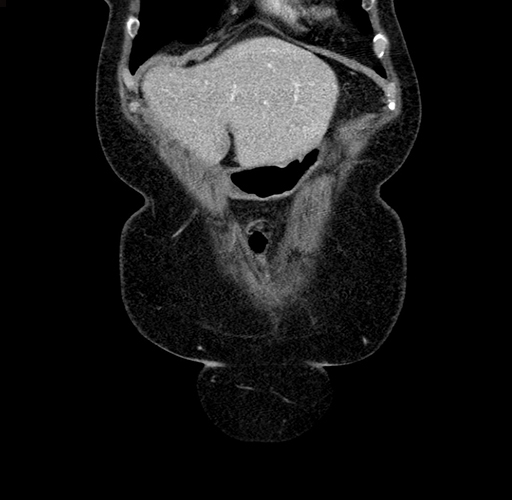

Pre-Chemo: Coronal Venous

Coronal Venous